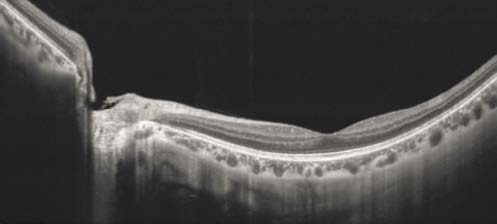

高速视网膜成像

典型应用 | 眼前段成像、内窥镜、皮肤科、心脏病学、无损检测等等 | 高速视网膜成像 | 生物测量断层扫描 | ||||||